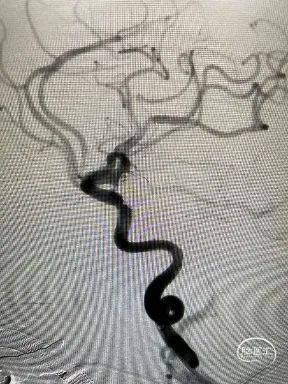

脑血管造影示左侧后交通大型动脉瘤,决定采用双微导管栓塞技术,由于病人的颈内动脉起始部呈360°血管成袢(图见于文中术后造影),故使用了Tethys®中间导引导管放置于岩段水平段。

术后工作角度

术后正位

术后侧位